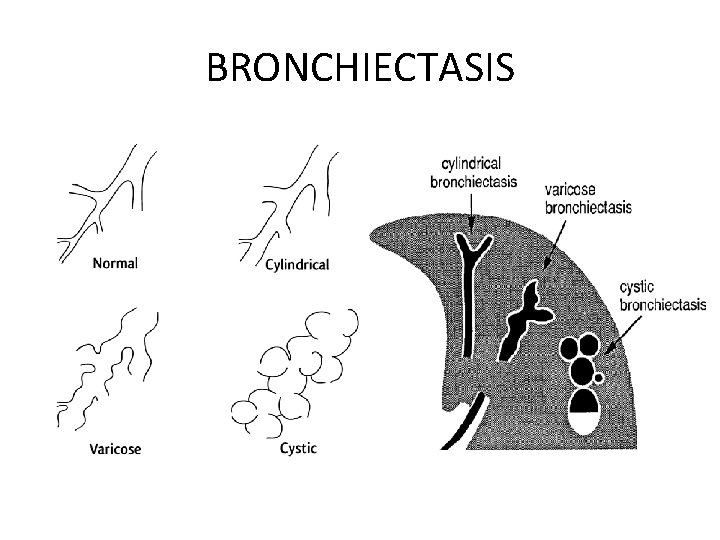

PATTERNS OF BRONCHIECTASIS Three different patterns of bronchiectasis have been described Ø Cylindrical bronchiectasis: the involved bronchi appear uniformly dilated Ø Varicose bronchiectasis: the affected bronchi have an irregular or beaded pattern of dilatation resembling varicose veins Ø Saccular (cystic) bronchiectasis: the bronchi have a ballooned appearance at the periphery, ending in blind sacs

BRONCHIECTASIS